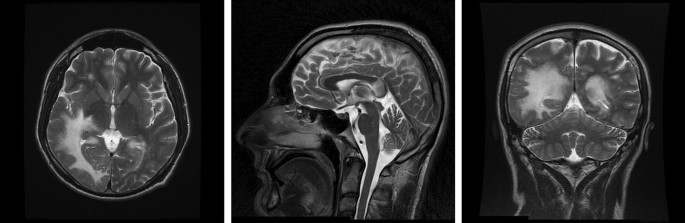

Rapid-progressing progressive multifocal leukoencephalopathy in two patients newly diagnosed with HIV: case series and review of literature - Journal of NeuroVirology

Source : https://link.springer.com/article/10.1007/s13365-023-01115-5

The JC Polyomavirus (JCPyV) is a virus of global distribution and is usually kept under control by the immune system. In patients with AIDS, a latent JCPyV infection can reactivate...

Conclusions: Patients with neurological symptoms must be a matter of great concern to all doctors. They should be tested for HIV and examined with an MRI of the brain paired with CSF evaluation earlier even with slight clinical lesions. Treatment that targets JCPyV directly is needed and would be highly beneficial for patients with PML,...